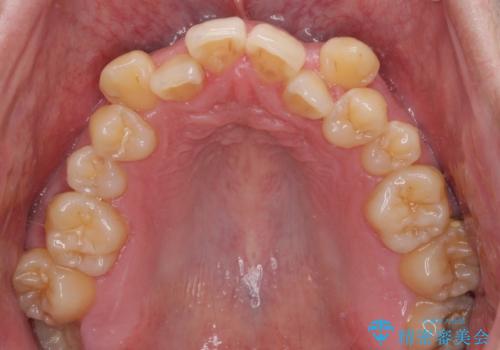

八重歯とクロスバイト 目立たないワイヤー装置で矯正治療

- 八重歯と前歯のクロスバイトを改善したいとのことで来院された患者様です。

デコボコの程度は強かったのですが、口元の突出感はなかったため、非抜歯矯正としました。

デコボコが解消されると歯列が拡大される方向に動くため、出っ歯のような仕上がりとなることがあります。舌の突出癖を改善するトレーニングをしっかりと行っていただくことで、突出を抑制することができます。